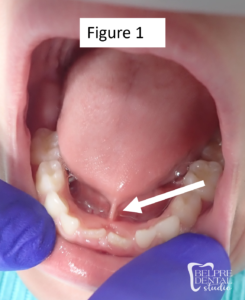

Sometimes tongue ties are easy to spot with an untrained eye. In Figure 1 below we can see a Kotlow Class IV anterior tongue tie. The white arrow points to the frenulum which has string-like appearance. Posterior tongue ties are more difficult to diagnose due to their position beneath the mucous membranes at the bottom of the mouth. Only medical professionals with specialized training can diagnose them. In Figure 2 below we can see an example of a posterior tongue tie. Keep in mind that TOTS must be assessed and diagnosed based upon function, meaning what they look like is less important than how they can move and what symptoms are present. A posterior tie may look very similar to a normal, well-functioning tongue. These are sometimes called “hidden” tongue ties.